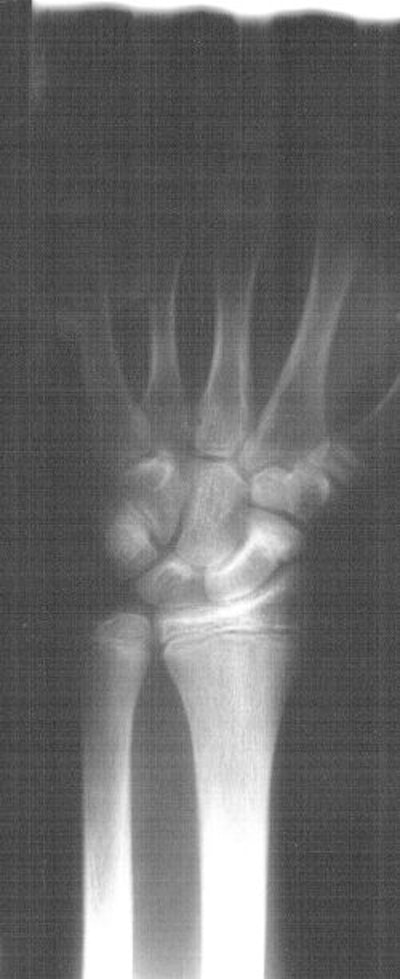

![]() |

| Six weeks post-injury scaphoid fracture. |